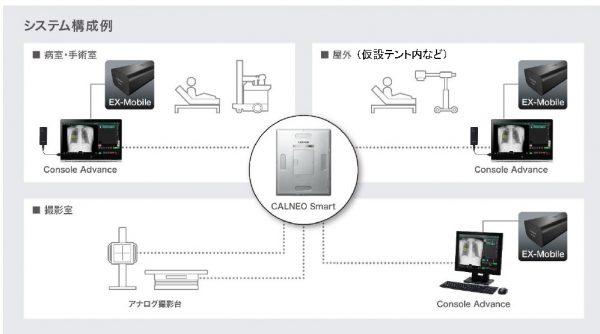

〈使用構成例〉

①カセッテDR+EX-Mobile

当社のカセッテDR「FUJIFILM DR CALNEO Smart(カルネオ スマート)」シリーズおよび 「FUJIFILM DR CALNEO Flow(カルネオ フロー)」シリーズと連携できる。X線撮影室や病室で撮影した後に、CXR-AIDの解析結果をコンソール上で確認可能だ。また、すぐにPACSへ元画像と共に解析結果画像を転送でき、読影医の速やかな画像診断を支援する。さらに、救命救急室や隔離病棟など病院内外複数の場所で使用することもできる。

カセッテDR+EX-Mobileによるソリューション例

②「CALNEO Xair」+EX-Mobile

「CALNEO Xair(カルネオ エックスエアー)」は在宅医療などにおいて簡単なX線検査を実現する携帯型X線撮影装置だ。「EX-Mobile」を接続したカセッテDRを利用する事により、在宅診療、災害現場など幅広いシーンにおいて、X線撮影後、その場でCXR-AIDの解析結果を確認することができる。

③C@RNACORE+EX-Mobile

解析結果は、撮影した元画像と共に汎用画像保管診断装置(PACS)に転送が可能で、医師が画像診断ワークステーション上で診断を行う際に解析結果を補助情報として利用できる。当社のクリニック向け画像診断ワークステーション「C@RNACORE(カルナコア)」にも対応しており、クリニックの医師が「C@RNACORE」上で画像診断を行う際に、CXR-AIDの解析結果を参照することで、異常所見の見落とし防止を支援する。「C@RNACORE」に「EX-Mobile」を接続することで、DRカセッテのみならずCRシステム※5を含む汎用X線撮影装置で撮影した画像を解析することが可能だ。